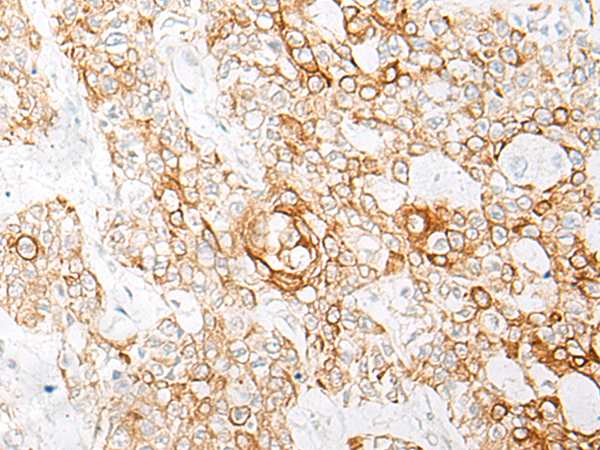

ELISA, IHC |

IHC positive control: |

Human esophagus cancer; Human prostate cancer |